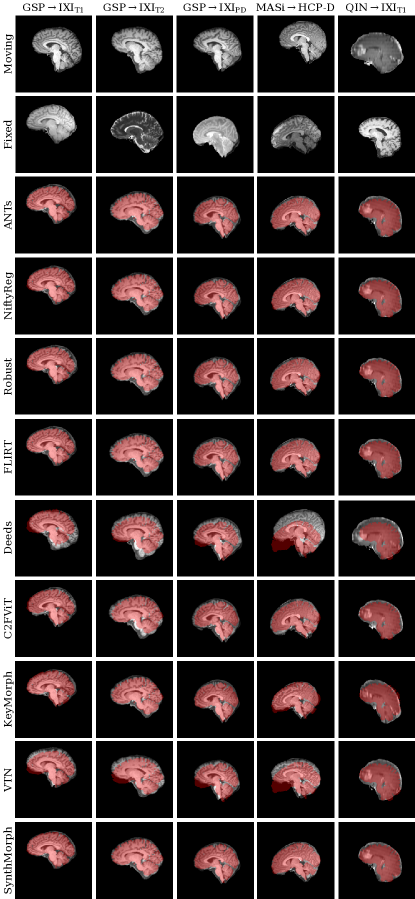

4.5.2 Results

Figure 8 shows representative registration examples for the tested dataset combinations, while Figure 9 quantitatively compares affine registration accuracy across skull-stripped image pairings. Although affine SynthMorph has not seen any real MRI data at training, it achieves the highest Dice score for every dataset tested.

For the GSPIXIT1 and MASiHCP-D pairs that most baselines are optimized for, SynthMorph exceeds the best-performing baseline NiftyReg by points ( and for paired two-sided -tests). Across all other pairings, SynthMorph matches the Dice score achieved by the most accurate affine baseline, which is NiftyReg in every case.

Deeds performs least accurately, lagging behind the second last classical baselines by or more. The other classical methods perform robustly across all testsets, generally within 1–2 Dice points of each other.

On the MASiHCP-D testset, FLIRT’s performance exceeds Robust by () and matches it across GSPIXIT1 pairs (). Across the remaining testsets, FLIRT ranks fourth among classical baselines.

In contrast, the DL baselines do not reach the same accuracy. Even for the T1w pairs they were trained with, SynthMorph leads by or more, likely due to domain shift between the test and baseline training data. As expected, DL-baseline performance continues to decrease as the test-image characteristics deviate further from those at training. Interestingly, VTN consistently ranks among the least accurate baselines, although its preprocessing effectively initializes the translation and scaling parameters by separately adjusting the moving and fixed images such that the brain fills the whole FOV.

Even though affine SynthMorph does not directly optimize image similarity at training, it surpasses NiftyReg for GSPIXIT1 () and MASiHCP-D () pairs in terms of the image-based NCC-MIND metric. Generally, NCC-MIND ranks the methods similarly to Dice overlap, as does NCC (not shown) across the T1w registration pairs.

Figure 12 compares the drop in median Dice overlap the affine methods undergo for full-head as opposed to skull-stripped GSPIXIT1 images. Except for Deeds, brain-specific accuracy reduces substantially, by 3% in the case of NiftyReg and up to 8% for ANTs. Affine SynthMorph remains most robust: its Dice overlap changes by less than 0.05%. Deeds is the only method that sees accuracy increase but still yields the lowest score for the testset.

4.6.2 Results

Figure 13 shows typical deformable registration examples for each method, and Figure 14 quantitatively compares registration accuracy across testsets in terms of mean Dice overlap over the 21 largest anatomical structures (large-21), 10 fine-grained structures (small-10) not optimized at training, and image similarity measured with NCC-MIND. Supplemental Figures S.1–S.5 show deformable registration accuracy across individual brain structures.

Although SynthMorph trains with synthetic images only, it achieves the highest large-21 score for every skull-stripped testset. For all cross-contrast pairings and the pediatric testset, SynthMorph leads by at least 1.7 Dice points compared to the highest baseline score (MASiHCP-D, for paired two-sided -test) and often much more. Across these testsets, SynthMorph performance remains largely invariant, whereas the other methods except Deeds struggle. Crucially, the distribution of SynthMorph scores for isotropic data is substantially narrower than the baseline scores, indicating the absence of gross inaccuracies such as pairs with that several baselines yield across all isotropic contrast pairings. On the clinical testset QINIXIT1, SynthMorph surpasses the baselines by at least . For GSPIXIT1, it outperforms the best classical baseline ANTs by 1 Dice point ().

Across the T1w testsets, FNIRT outperforms NiftyReg by several Dice points and also ANTs for MASiHCP-D pairs. Surprisingly, FNIRT beats NiftyReg’s NMI implementation for GSPIXIT2, even though FNIRT’s cost function targets within-contrast registration. The most robust baseline is Deeds, which ranks third at adult T1w registration. Its performance reduces the least for the cross-contrast and clinical testsets, where it achieves the highest Dice overlap after SynthMorph.

The only joint DL baseline with trained weights that we had access to, VTN, yields relatively low accuracy across all testsets. This was expected for the cross-contrast pairings, since the model was trained with T1w data, confirming the data dependency introduced with standard training. However, VTN lags behind the worst-performing classical baseline for GSPIXIT1 data, NiftyReg, too (, ), likely due to domain shift as in the affine case.

Considering the fine-grained small-10 brain structures held out at training, SynthMorph consistently ranks among the two best-performing methods, matching the performance of Deeds for GSPIXIT1 (, ) and GSPIXIPD (, ), and leading by at least () on the clinical testset.

Interestingly, SynthMorph outperforms all baselines across testsets in terms of NCC-MIND (), although it is the only method not optimizing or trained with an image-based loss.